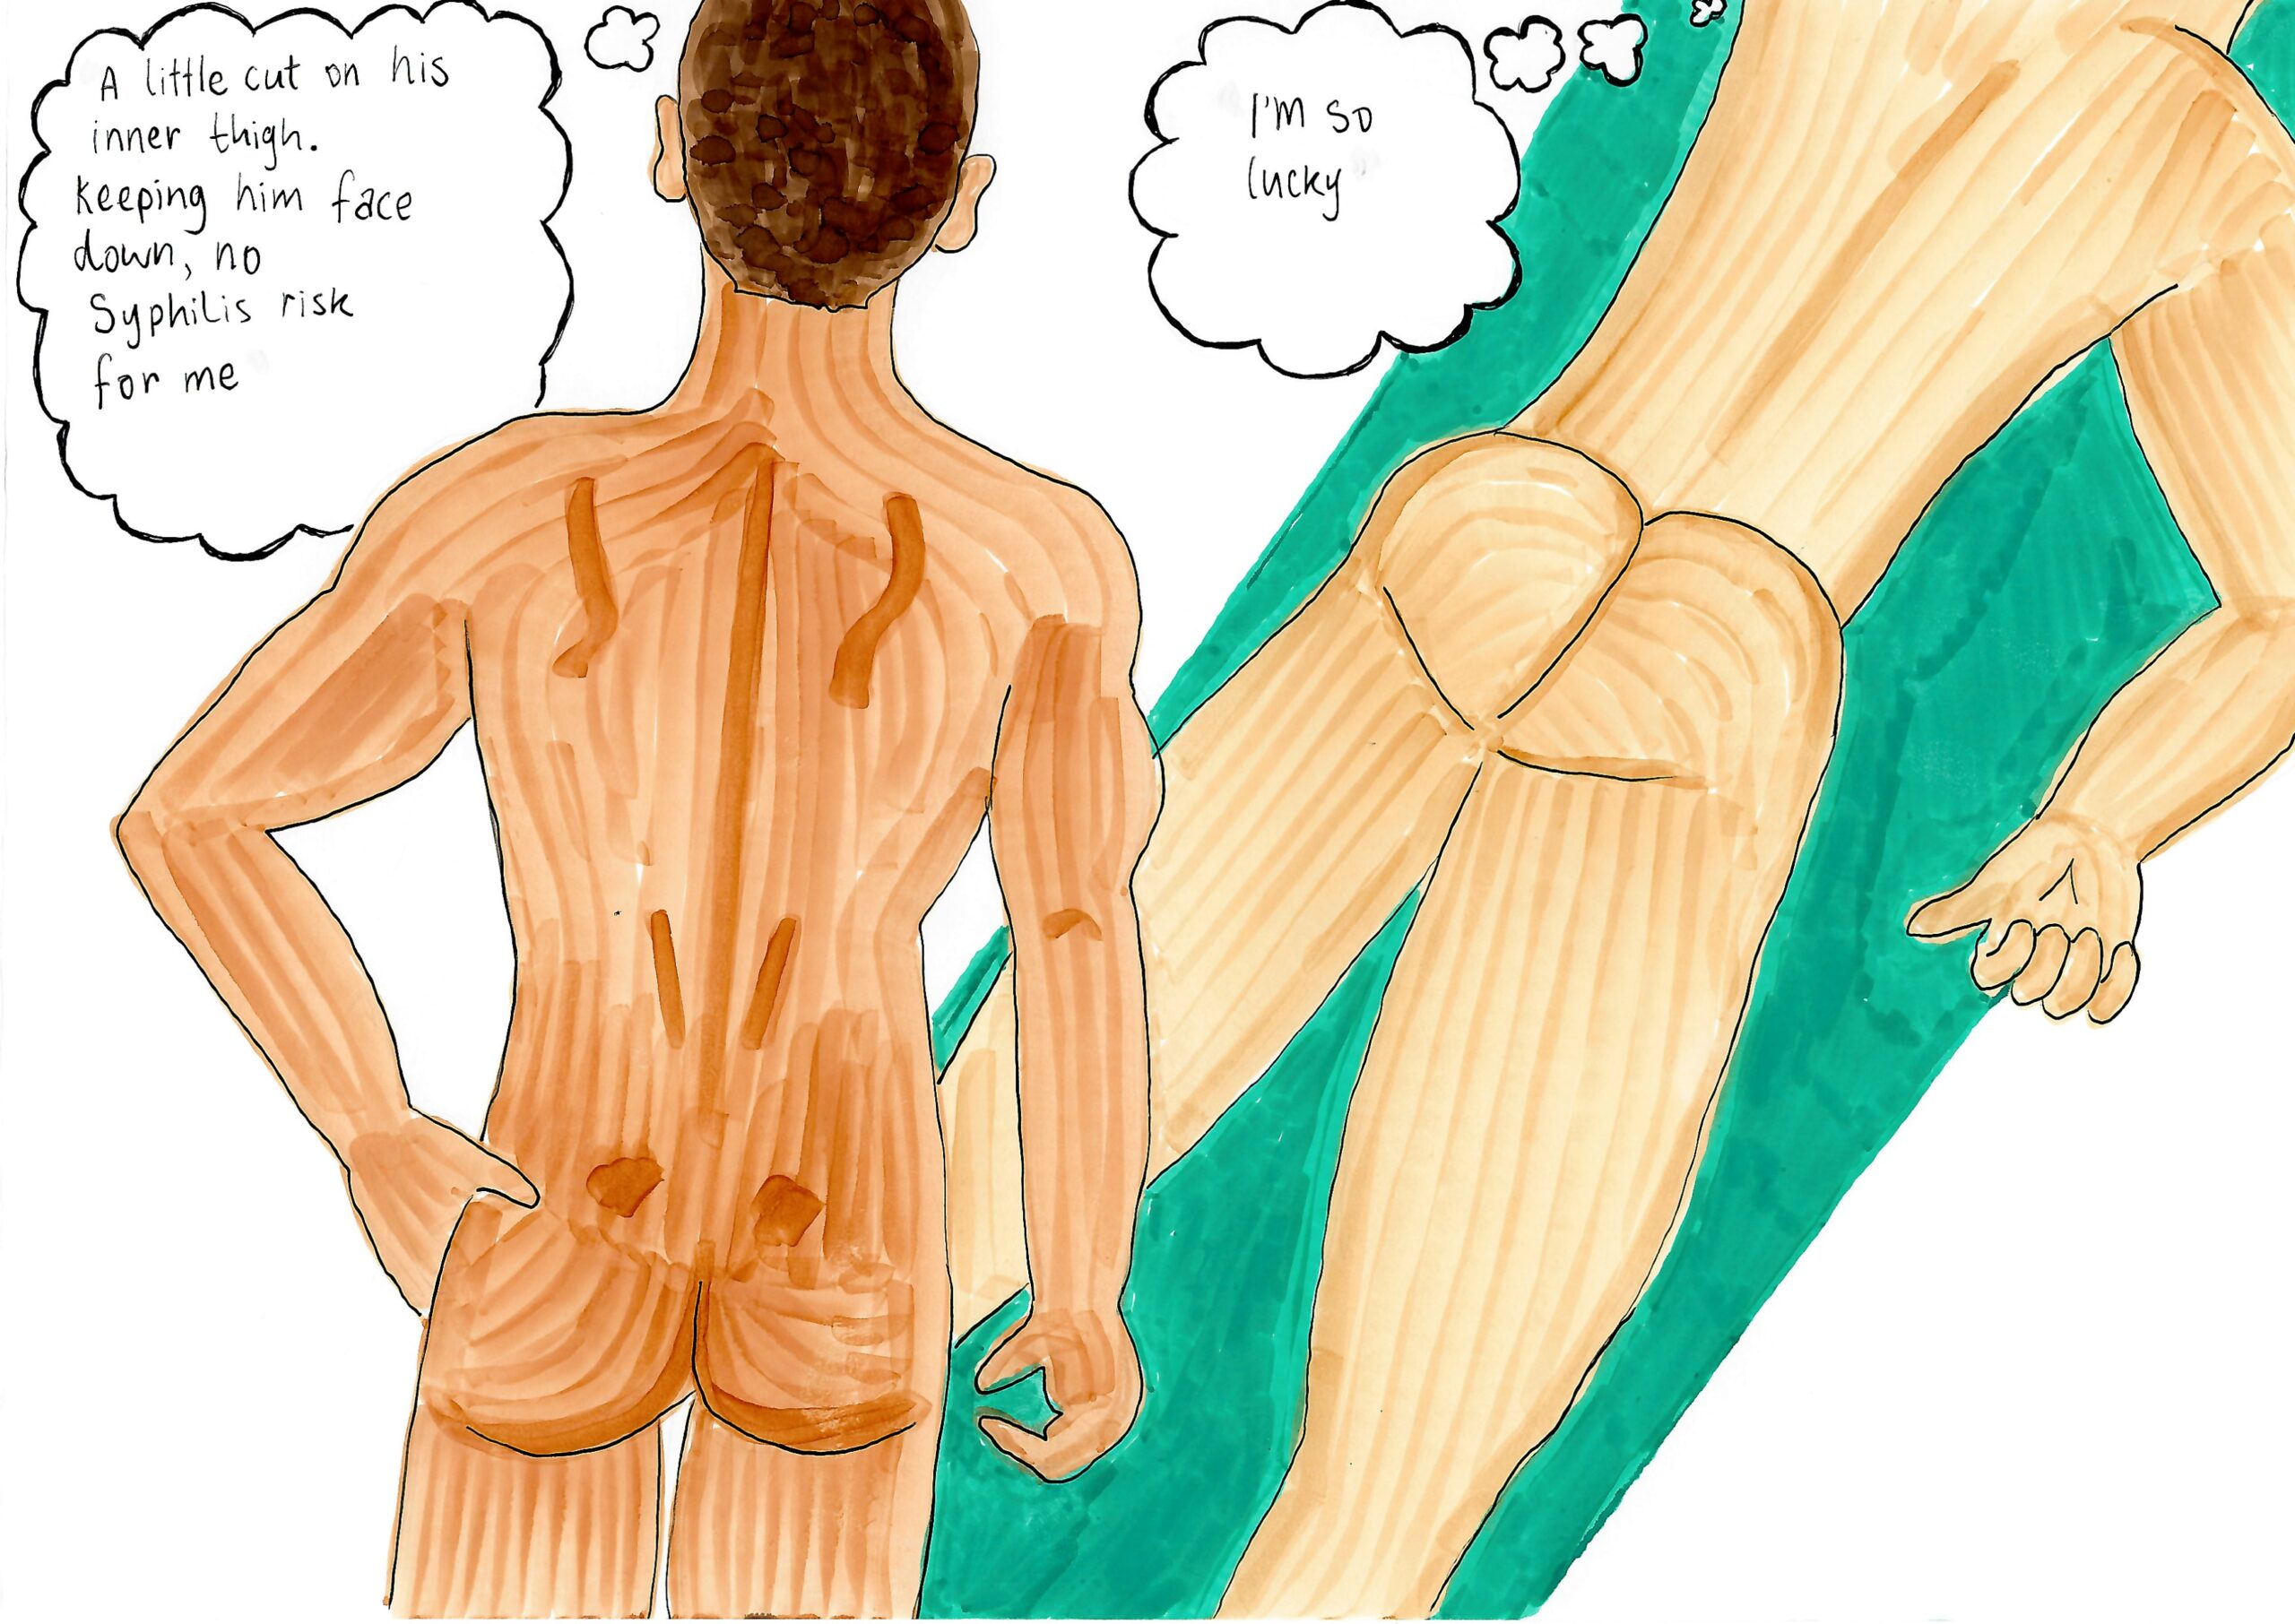

- Put a bandaid on anything that looks like a symptom of Primary Syphilis.

- Cover symptoms of Primary Syphilis with a towel.

- Do face-down body rubs and body slides to avoid genital contact with symptoms of Primary Syphilis.

Most sex workers are not currently familiar with Syphilis. It’s easy to overlook or ignore the symptoms of Primary Syphilis. Basically, it is hard to determine whether it is a symptom, or just a small cut or skin tag. Play it safe by using bandaids, washing hands, using towels and doing face-down massage and/or body slides. Sex workers are actually the only people using an STI visual screen—keep at it and you will gain confidence.